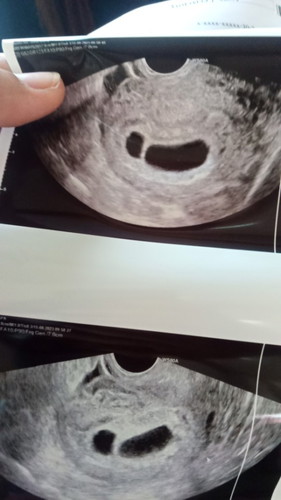

ตอนนี้ท้องได้ 8 สัปดาห์ ซาว์ดเจอถุงน้ำคร่ำ 2 ถุง แต่ยังไม่เห็นน้องเป็นอันตรายไหมคะ

8wยังไม่เจอตัว โอกาสท้องลมสูงมากค่ะแม่ อาจจะต้องซาวทางช่องคลอดเพื่อให้ได้ผลที่ชัดขึ้น